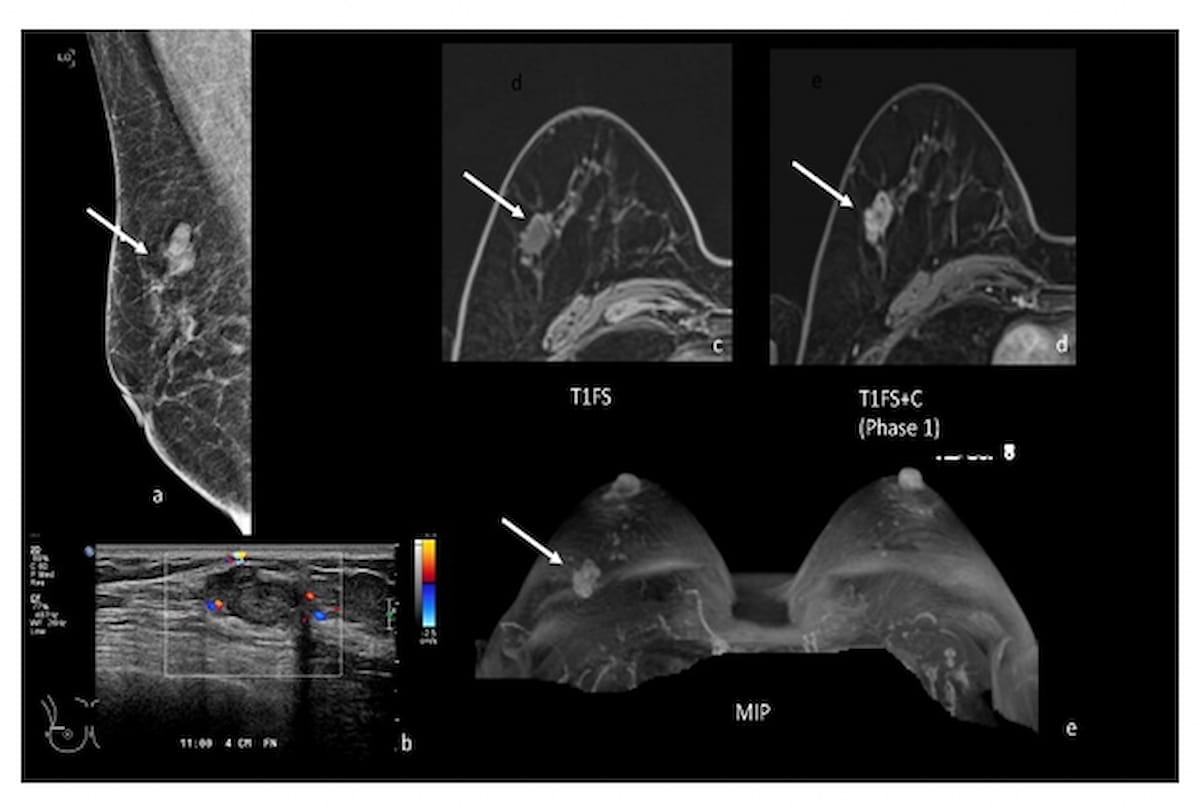

In a recent interview, Vivianne Freitas, M.D., discussed new research findings on positron emission mammography (PEM), pertinent benefits of the technology and its potential as a viable alternative in the future to conventional imaging techniques for breast cancer screening.

Findings from a new pilot study showed that low-dose positron emission mammography (PEM) detected 96 percent of malignant index lesions and had a 46 percent lower false-positive rate in comparison to breast MRI.